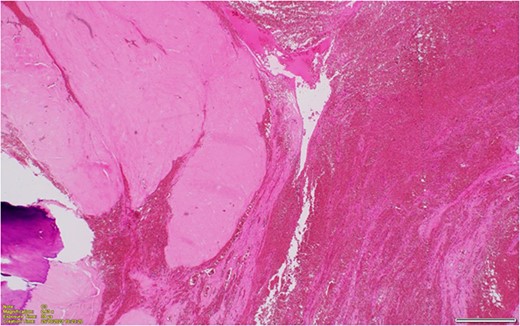

A midline laparotomy was performed with both members of general surgery and gynaecology present. Findings were notable for a bulky uterus that had torted 1080° on the cervical pedicle. This was associated with a perforated uterus at the anterior lower segment that was actively bleeding. A small portion of small healthy bowel was adhered to the uterus, however there were no evidence of widespread intra-abdominal adhesions. There was no evidence of malignancy. A pinpoint cervix was noted with no evidence of vaginal bleed. Blunt dissection freed the uterus from the small bowel and the uterus was detorted. Ligasure dissection was performed of the bilateral infundibulopelvic ligament ligaments, and uterus amputated above the cervix for haemostasis. A completion total hysterectomy and bilateral salpingo-oophrectomy was then performed. The patient was extubated 2 days post laparotomy, and stepped down to the ward. Both nasogastric tube and in dwelling catheter were removed on day 3 post laparotomy with resumption of bowel function. The patient was discharged on day 8 post laparotomy with ongoing nutritional supplementation. Histopathology demonstrated hyalinized and calcified leiomyoma with adjacent haemorrhagic infarction of the uterine wall, in keeping with torsion (Figs 2 and 3). Subsequently, in her 8 week follow up, she has done markedly well, and has returned to pre-morbid functioning.

Hyalinized and calcified leiomyoma with adjacent haemorrhagic infarction of the uterine wall, in keeping with torsion.